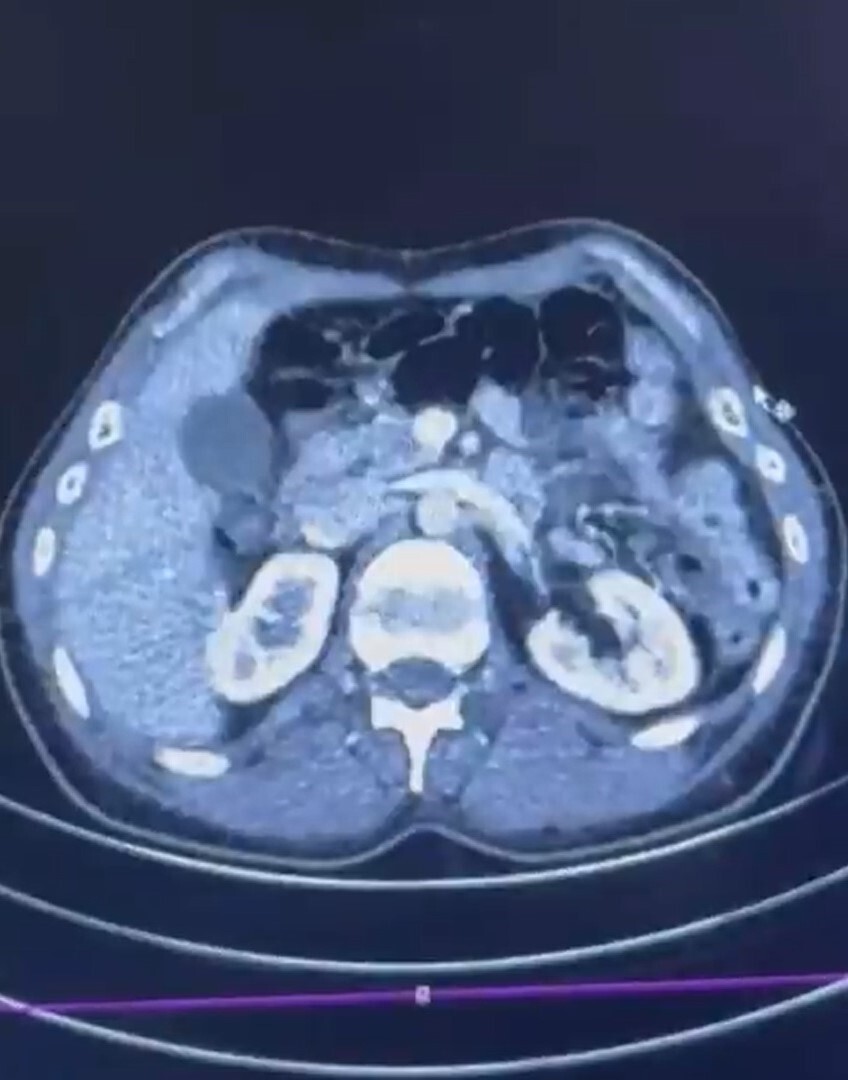

Operasyonda S.C., R.B.C. ve G.M. yakalandı. Kayseri Şehir Hastanesi'nde yapılan iç beden muayenelerinde, S.C. ve R.B.C.'nin mide kısımlarında bulunan 50 adet kapsül halinde toplam 554 gram uyuşturucu madde ele geçirildi.

ŞÜPHELİLERİN MİDESİNDE KAPSÜL ŞEKLİNDE YARIM KİLO UYUŞTURUCU MADDE ELE GEÇİRİLDİ.